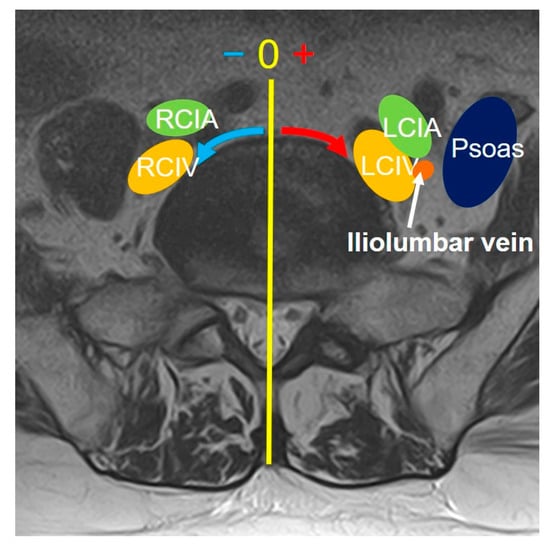

Over 220 patients underwent OLIF51 or LCA surgery from 2016 to 2023, and 43 patients were included in this study. There were 16 males and 27 females with an average age at surgery of 60.4 (37–80) years old. The average body height, weight, and body mass index were 160 cm (146–187), 60.4 kg (41–86.9), and 23.5 (16.7–33.3). The disorders of patients included L5 isthmic spondylolisthesis, foraminal stenosis at L5/S1, degenerative disc disease, and pseudarthrosis of transforaminal interbody fusion at L5/S1. The infectious disease or any pathologies receiving previous retroperitoneal surgeries around lumbosacral area were excluded. All cases received preoperative lumbosacral MRI scans (Phillips Ingenia 3.0T, Canon Excelart Tiatan 1.5T) in a supine position. Before starting the OLIF51 surgery, intraoperative vein-enhanced CT (O-arm O2, Medtronics, MN, USA) was taken in the right decubitus position (Figure 1). All surgeries were performed by a single senior surgeon at a single institution.

2.3. Intraoperative Evaluation of Vein Anatomy in the Right Decubitus Position on Enhanced CT

The intraoperative vein anatomy in the right decubitus position was evaluated with vein-enhanced intraoperative CT (O-armO2, Medtronics) (Figure 1C). Prior to the incision made for OLIF51 surgery, the contrast medium was injected from the peripheral vein of left foot, and a O-arm 3D scan was subsequently taken. The axial and sagittal positions of the vein structure surrounding the L5/S1 disc were measured according to the same parameters as those in the supine position on MRI (Figure 2). The vein position on intraoperative CT was subsequently compared to that in the supine position on MRI, and the movement of the vein structure was quantitatively analyzed (Figure 2 and Figure 4).

Figure 1. (A): OLIF51 surgery setup. A specially designed triple-arm retractor was used for safe retraction of vascular tissue, exposing the L5/S1 disc. (B) Preoperative MRI axial scan in the supine position at the L5 caudal endplate level. (C) Intraoperative enhanced CT scan in the right decubitus position at the L5 caudal endplate level.